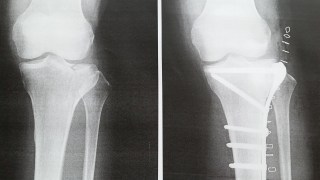

骨折日記14:脛骨高原骨折 術前・術後 チタン入

3週間前のあの日、病院に来て看護師さんは見るなり「折れている感じですね。」の一言。笑顔の素敵なK医師も「折れていそうですね。レントゲン撮ってみましょう。」とレントゲンを撮って説明してくれたのですが、素人には、「これってヒビじゃないの?」なん...